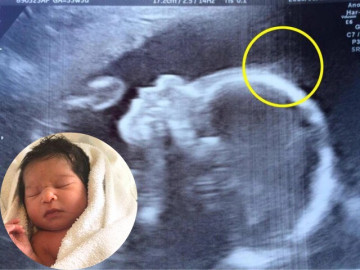

Bà bầu - Đến viện siêu âm, mẹ bầu giật mình thấy điểm lạ trên đầu con, cái kết bé gái sinh ra đã nổi tiếng vì quá xinh